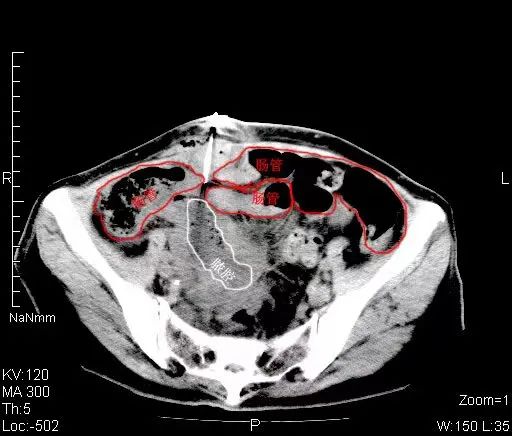

影像科穿刺团队郝申、张勇猛医师阅片后发现,此处脓肿位于盆腔深部,前方肠管横跨,几乎无进针路径;后方及侧方髂骨及骶骨遮挡,无法进针。

严金明主任指示可利用肠管蠕动,寻找通路。

遂选择同轴活检针,将内芯抽出,只用无尖锐的钝头缓慢进针并注射生理盐水,试图冲开前方肠管,寻觅间隙,打开通道。最终成功置入导管,引流出黄褐色脓液,引流通畅,患者安全返回病房。